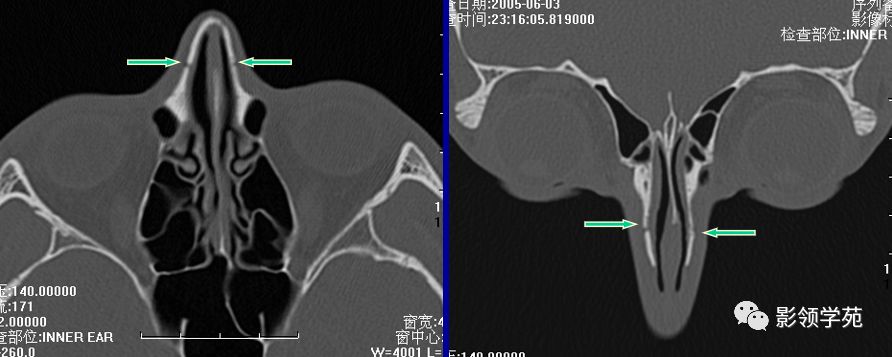

双侧鼻骨骨折

双侧上颌骨额突骨折

鼻中隔骨折